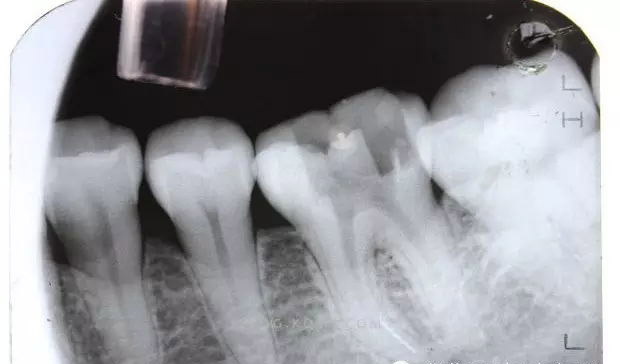

(1)通路建立:臨床操作中,X線明確斷針位置后,在根管顯微鏡(放大10~20倍)觀察下,先用帶柄根管銼插入根管,直到斷針冠方斷面,用止動(dòng)片標(biāo)記,確定斷針深度。然后用K銼或者H銼將斷針上部的根管預(yù)備到30~40#,將GG鉆2#和3#尖 端磨平,使GG鉆尖 端平面的直徑大于斷針的直徑,用2?;蛘?#調(diào)磨后的GG鉆從根管口預(yù)備到斷針的位置,建立通道,使斷針以上部分根管明顯通暢,便于顯微鏡觀察和術(shù)中操作。

首先,是斷針?biāo)幐苌疃?,橫截面直徑和根管彎曲度。一般情況下,如果能暴露折斷器械長(zhǎng)度的1/3,常可以取出;如果折斷器械處于比較直的根管中比較容易取出;如果折斷器械部分處于根管彎曲處,并且牙本質(zhì)厚度容許建立從根管口到器械冠方的通道,斷針也是可能被取出的:但是如果斷針處于根管彎曲處以下至根尖區(qū),則是很難建立安全的通道,折斷器械很難取出。